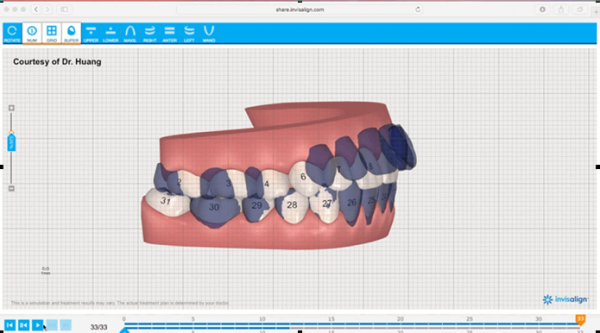

偷拍的高科技扫描仪,医生说不仅更舒适精确度也大大大提升哦!扫描完之后就会有一个完整的牙齿模型,和非常非常粗略的预期矫正效果。医生会根据你的预期,在咬合正确的最大程度上实现美观,不仅是牙齿,还有脸型的要求,来设计一个精确的,完整的方案。

偷拍的高科技扫描仪,医生说不仅更舒适精确度也大大大提升哦!扫描完之后就会有一个完整的牙齿模型,和非常非常粗略的预期矫正效果。医生会根据你的预期,在咬合正确的最大程度上实现美观,不仅是牙齿,还有脸型的要求,来设计一个精确的,完整的方案。 看完整个动图之后我虽然很开心,但是还是满心疑惑,我的牙齿真的会变成这样吗?是怎么做到的呢?

看完整个动图之后我虽然很开心,但是还是满心疑惑,我的牙齿真的会变成这样吗?是怎么做到的呢?